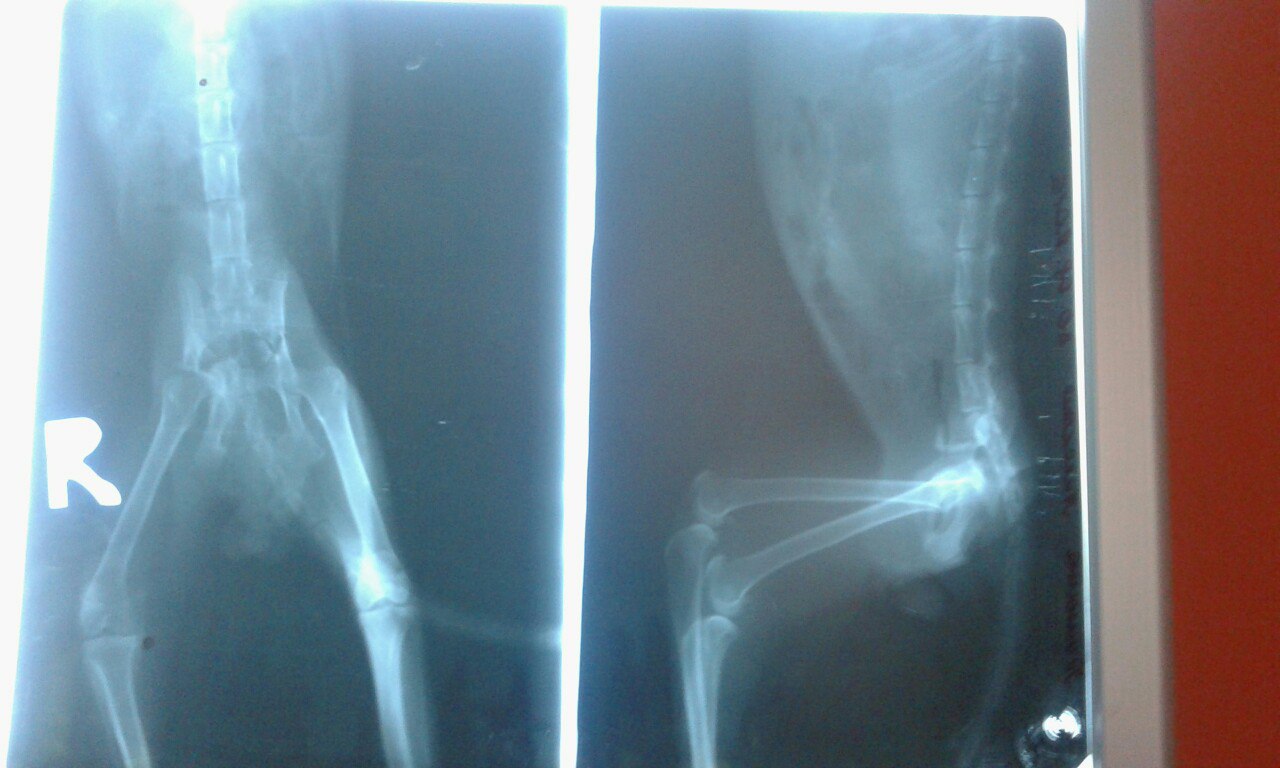

Девушка,которая его нашла,ходила к врачу. Предварительный диагноз: Паралич задних лапок, перебит или перекусан хвостик, сильное нагноение! Гной выделяется из прямой кишки!!! Его облепили мухи и уже три дня откладывают личинки......Он не ест и почти не пьет..... Ему нужна срочная помощь!!! Остальные диагнозы мы узнаем после того как у него возьмут анализы и тщательно осмотрят в клинике!